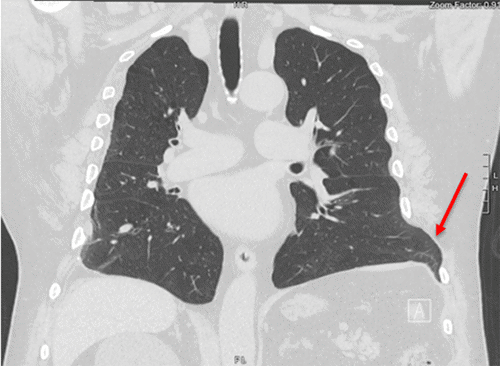

He had significant comorbidities, including atrial fibrillation, type 2 diabetes, hypertension, hypothyroidism, gout, obesity (BMI 31),1 asthma, 25 pack-year smoking history, COPD, history of remote polysubstance abuse, and chronic pain. On clinical exam, the patient had evident disruption of his costal margin with respiration and at rest upon palpation. Manipulation of his costal margin rupture aggravated his pain. During his intake visit, the patient underwent a CT scan, from which he was diagnosed with a costal margin rupture with an associated intercostal hernia between ribs 7 and 8 (Figure 1).

Figure 1. CT Scan Showing Patient's Left Intercostal Hernia (arrow indicates defect). Published with Permission